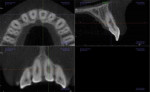

While the exact prevalence of internal resorption is not well known,2 it is regarded as a rare and incidental finding, with approximately only 2% of cases presenting with symptoms.3 Several studies have reported that routine radiography does not always detect the presence of a resorptive lesion and does not show its true size.2,4,5 Recently, cone-beam computed tomography (CBCT) has gained popularity in endodontic diagnosis and treatment planning due to its ability to produce a 3-dimensional image allowing the clinician to evaluate the true nature and severity of the lesions.1,5 Treatment of resorptive lesions is very predictable and successful as long as the lesion does not perforate the canal walls.3,6

The initial clinical examination showed an intact crown with no caries or restorations present and a vital pulp. However, periapical radiographs revealed a well-defined symmetrical radiolucency, which ballooned out of the pulp chamber (Figure 2). No periapical lesion or widening of the periodontal ligament space was found. The patient had an endodontic consultation, which included an intraoral examination, shifted periapical radiographs, and a CBCT image (Figure 3), to assess the presence and type of resorption. CBCT imaging is crucial in differentiating between internal and external resorption and determining the extent of the lesion, which will affect the treatment plan and outcome.1,5

Internal resorption is inherently difficult to diagnosis because of its insidious nature and varying clinical presentation. It has been established that intraoral radiographs reveal limited information, which can lead to misdiagnosis and ineffective management of resorptive lesions.5 In recent years, a useful diagnostic tool has emerged for assessing the presence, type, and extent of resorptive lesions. CBCT allows the clinician to view the anatomy in three dimensions to confidently diagnose and manage the defect.1,5 For a non-perforating internal resorption defect, NSRCT is the treatment of choice and has been proven to have a high degree of success.6